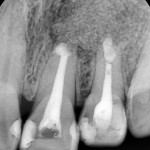

2013-06-19 초진 #21,22

작은 사진을 찍어 보았습니다. 중절치는 예전에 신경치료를 받으셨고 측절치는 신경치료가 되어 있지 않았습니다. 그리고 두 치아 사이가 어두운 색으로 보이는 부분이 있는데  이로써 잇몸뼈가 차있지 않음을 다시 확인할 수 있었습니다. 일단 먼저 측절치의 신경치료를 진행하면서 예후를 관찰해 보기로 하였습니다.  그런데 신경치료 후에도 염증의 사이즈가 줄어들지 않아서 치근단수술을 진행하기로 하였습니다.